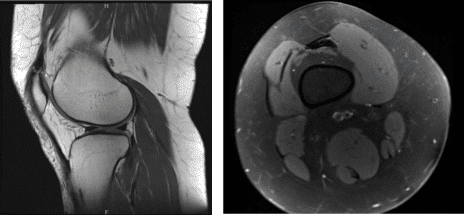

Los resultados de la resonancia magnética del paciente mostraron un desgaste condral mínimo sobre la rótula y la meseta tibial lateral. No hay evidencia de desgarros meniscales. Tendinosis rotuliana leve.

Resonancia magnética de rodilla derecha sin contraste